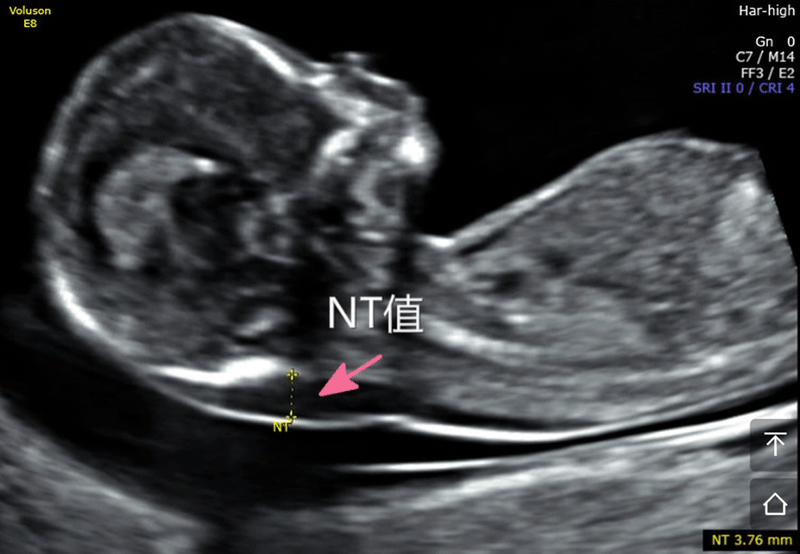

nt是胎儿颈后透明袋的简称,全称为(nuchal teanslucency),nt检查就是胎儿颈后透明带检查,检查胎儿颈后部皮下组织内液体积聚的厚度。

nt检查的主要作用就是获得nt值,通过nt值诊断胎儿是否正常,是否有染色体疾病和其他原因造成胎儿畸形,如果通过nt值提示胎儿有异常,在做四维彩超和唐氏筛查的时候将会重点关注。

nt检查正常值一般是在≤2.5mm,只要通过nt检查发现nt值在正常值范围内,就可不用担心了,nt检查属于一次检查。